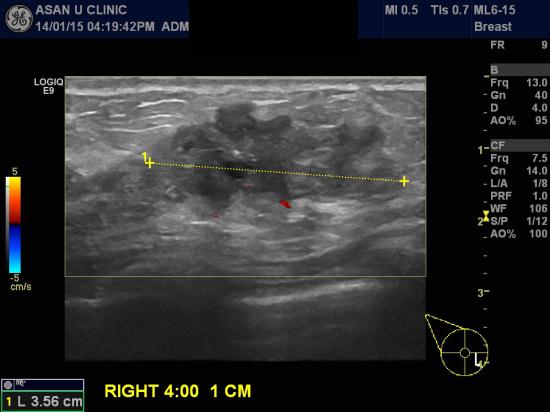

아산유외과 개원 후 58번째 유방암 진단.

우측유방에 갑자기 멍울이 만져지고 유두에서 피가 나와 내원한 37세 여성분입니다.

초음파상 3.56cm의 혹이였으며

중심핵생검상 유방의 침윤성 유관암으로 판명되었습니다.

혹의 크기가 큰 경우라

유방 MRI, PET scan등의 추가검사가 요망됩니다.

조기진단이 최선의 치료입니다.